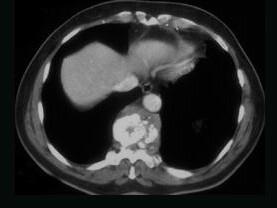

问题 女,34岁,发热,背部疼痛1个月余,请结合影像学检查,选出最可能的诊断 ( )

选项 A、脊椎转移瘤 B、骨髓瘤 C、脊椎结核 D、骨髓炎 E、椎体压缩骨折

答案 D